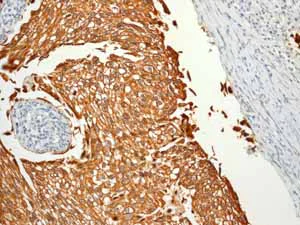

Immunohistochemistry (Formalin/PFA-fixed paraffin-embedded sections) analysis of human urinary bladder transitional carcinoma tissue labelling Cytokeratin 7 with unpurified ab68459.

Perform heat mediated antigen retrieval before commencing with IHC staining protocol.